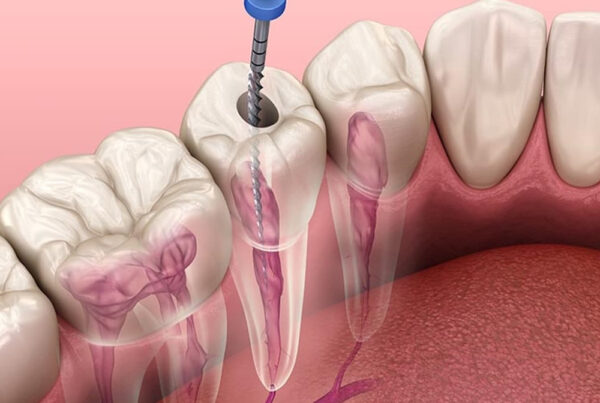

Periodontitis; diş ve dişi destekleyen dokuların (periodontal ligament, sement, alveol kemiği) yıkımıyla karakterize iltihapsal bir hastalıktır. Diş eti iltihabı, alveol kemiğine (çene kemiği) kadar ilerlemiştir. Periodontitisin temel nedeni; bakteri plağıdır ve mekanik olarak tedavi edilebilir. Ancak genetik, çevresel ve sistematik faktörler de hastalığın oluşmasında etken olabilir. Sistemik faktörler içinde diabet, kalp damar hastalıkları, epilepsi, down sendromu, AIDS ve kan hastalıkları sayılabilir.

Dişhekimleri dişetlerinin genel görünümünden şüphelendikleri zaman ‘periodontal sonda’ adı verilen bir alet ile diş ile dişeti arasındaki dişeti cebinin boyunu ölçerler. Ayrıca dişlerin etrafındaki kemik dokusunu değerlendirmek için röntgen filmler alınabilir. Böylece dişeti hastalıkları teşhis edilir.

Periodontal tedavinin ana amacı ise umutsuz gibi görünen sağlıksız dişleri ağızda tutmaktır. Hastalığın tipi ve şiddetine göre değişik tedavi yöntemleri uygulanabilir. Bunlar; öncelikle ağız hijyeni eğitimi, diş taşı temizliği, kök yüzeyi düzleştirilmesi, rejeneratif, rekonstrüktif ve mukogingival operasyonlar olarak özetlenebilir. Aynı zamanda yüksek gülme hattı olan bireylerin diş eti estetiğini sağlamak da, periodontal tedavi kapsamındadır. Hastalığın tipi ve şiddeti, hastanın alışkanlıkları, hekimi ile yapacağı işbirliği, ağız hijyeninin standardı, tedavi planlaması ve başarısını doğrudan etkiler.